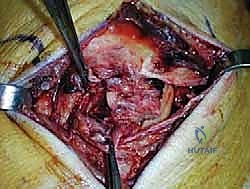

الخطوة الثالثة: الشق الجراحي والوصول الآمن

يتم عمل شق جراحي دقيق ومدروس على الجانب الداخلي للكاحل، خلف وتحت الكعب الإنسي. يستخدم الدكتور هطيف تقنيات تشريحية دقيقة لحماية الهياكل الحيوية المحيطة، وخاصة العصب الصافن (Saphenous Nerve) والوريد المرافق له، لتجنب أي تنميل أو ألم عصبي مزمن بعد الجراحة.

الخطوة الرابعة: تقييم وإصلاح رباط الدالية (Repair vs. Reconstruction)

بمجرد الوصول إلى رباط الدالية، يتم تقييم درجة التلف:

* الإصلاح المباشر (Direct Repair): إذا كانت أنسجة الرباط الممزقة ذات جودة جيدة (عادة في الإصابات الحديثة)، يقوم الدكتور هطيف بخياطتها مباشرة. يستخدم خطاطيف تثبيت عظمية (Suture Anchors) صغيرة جداً ومصنوعة من مواد متوافقة حيوياً (تذوب مع الوقت أو من التيتانيوم) لغرس الخيوط القوية في عظمة الكعب الإنسي، ثم يتم سحب الرباط الممزق وتثبيته بقوة في مكانه التشريحي الأصلي.